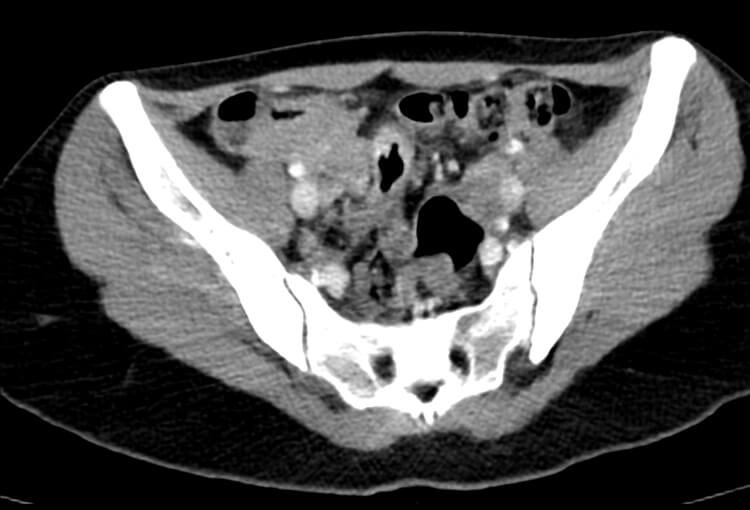

Before and After Denoising

120 kV / 20 mAs / 1 mm

Before FBP (Noise 189) VS After ClariCT.AI (Noise 46) 76% Denoising